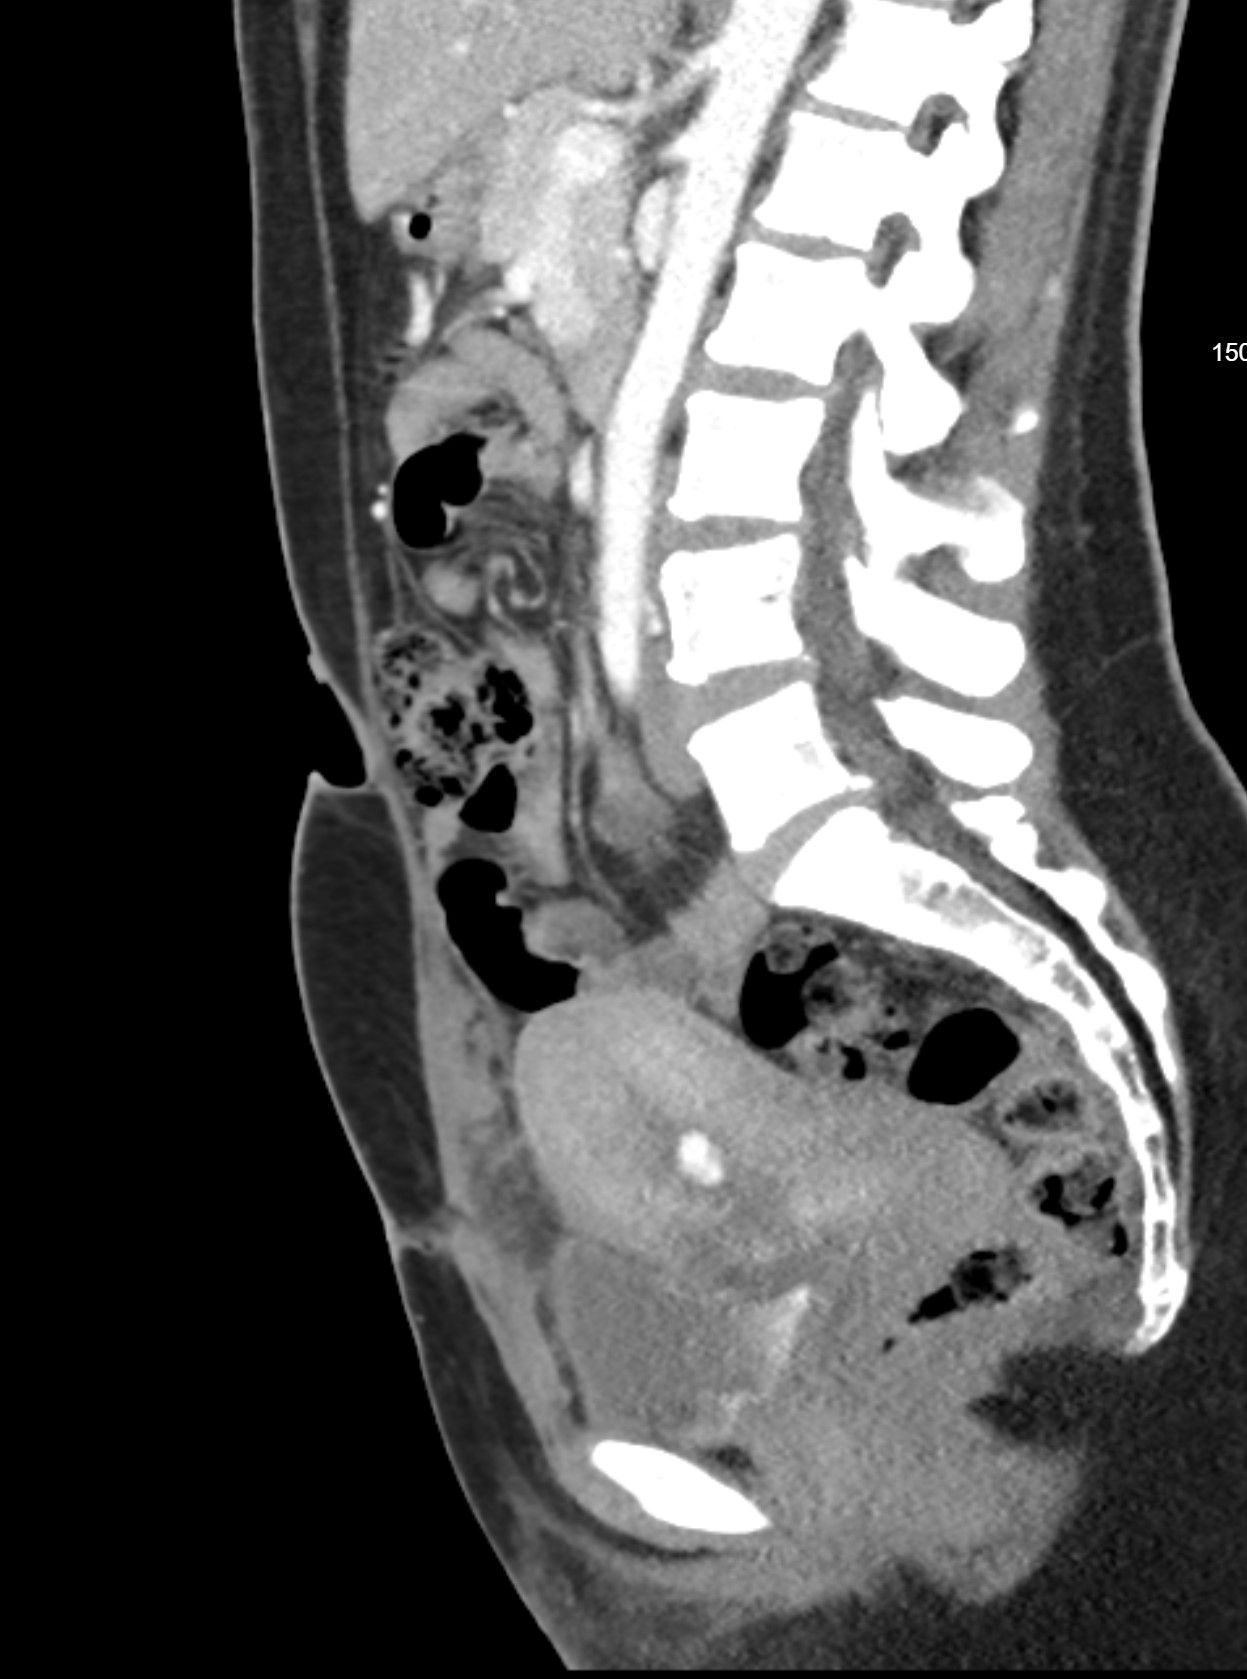

A 35-year-old female is two weeks postpartum after a caesarean section delivery. She presented to the emergency room with sudden brisk vaginal bleeding. What is the most likely diagnosis?